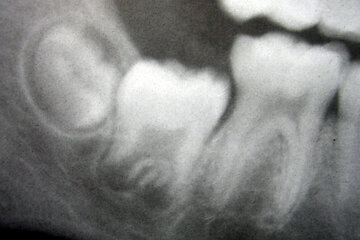

Врач Патлатая: хлоргексидин снимет боль при прорезывании «восьмерок»

Доктор Надежда Патлатая проинформировала, как правильно ухаживать за полостью рта при прорезывании зубов мудрости, пишет